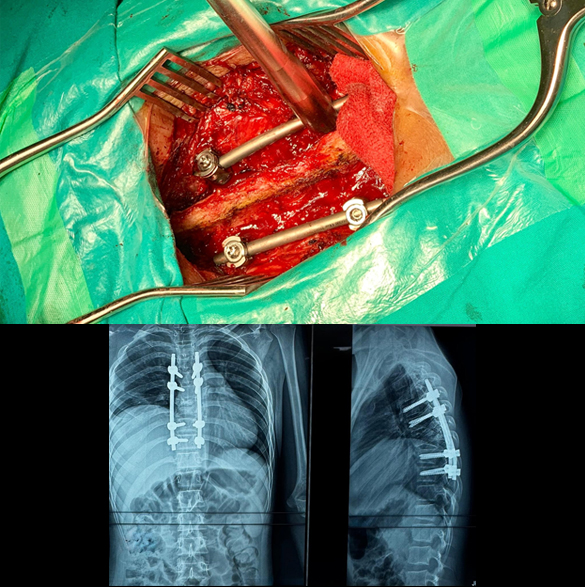

Spinal Fracture Fixation/Fusion (Open and Minimal Invasive Surgery)

Spinal fractures generally require spinal instrumentation (fixation with screws and rods) in most cases, to main the spinal alignment and future complications like paralysis and kyphosis. These procedures usually require opening of the spine at back and placing screws and rods at multiple vertebrae. Early surgery is a key in the outcome of spinal fractures, because delaying the surgery patient may develop paralysis (weakness in power of limbs). New techniques like minimal invasive surgery (MIS) where large skin incision is not used, can also be performed in some patients. Complications of fixation/fusion surgery may include wound infection, bleeding, and implants/screws improper placement.